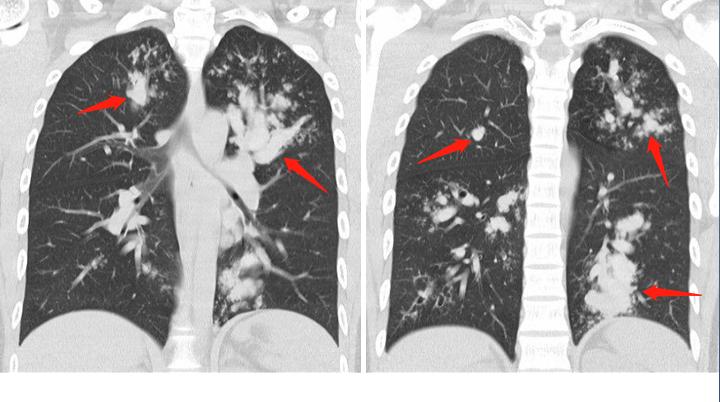

CT发现他的支气管多发扩张,箭头所示,像手指套一样白色迂曲的影子,这个叫“指套征”,周围还有一些白色小点片状浸润影,和一些小树芽征。

这种手指套样的改变,其实还可发生于肺结核、肺癌阻塞支气管等情况,为什么会直接考虑真菌感染呢?答案在下面这张图:

箭头区就是扩张的支气管,它有个典型特征是密度增高了,比血管的密度还高,提示里面有高密度的黏液栓,这是变应性支气管肺曲霉病(ABPA)的典型表现。

这种高密度黏液栓,是由于曲霉菌丝侵入小伙子气道后,引起变态反应,腺体分泌增加、炎细胞浸润,并且在菌丝作用下黏液变稠、浓缩,加上钙、金属粒子沉积形成(曲霉能富集空气中的铁、锰离子)。

见到这个高密度黏液栓,通常提示 局部炎症更严重,且容易复发。

除了上面这些表现之外,ABPA病人的CT片还有另一个常见的典型表现:病变游走性!一处病灶吸收,过一阵子另一叶肺里又出现新病灶。

这是因为机体不同部位对吸入的霉菌孢子产生变态反应的程度和时间有差异,或者再次吸入霉菌孢子引发新的变态反应有关。